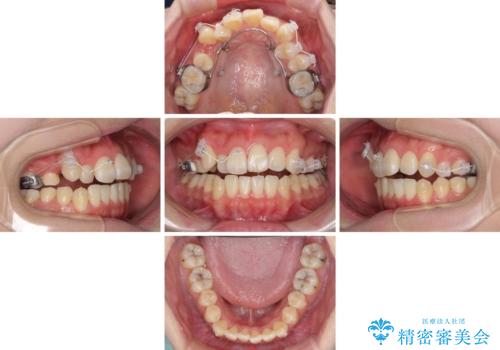

補助装置を使ったインビザラインによる抜歯矯正

- 八重歯と叢生を気にして来院された患者様です。

上下の前歯が非接触であり、叢生や八重歯が顕著であったため、上顎左右第一小臼歯2本を抜歯して排列することとしました。

抜歯により移動量が多くなるため、ワイヤーや補助装置を活用し、その後インビザラインによる矯正治療を行うこととしました。

元々奥歯に負担のかかる咬み合わせですり減っていたため、仕上がった歯並びでも奥歯が咬んでいないように見えましたが、実際にはしっかりと咬合しており、患者様本人も咬んだ感触に違和感はないとのことでした。